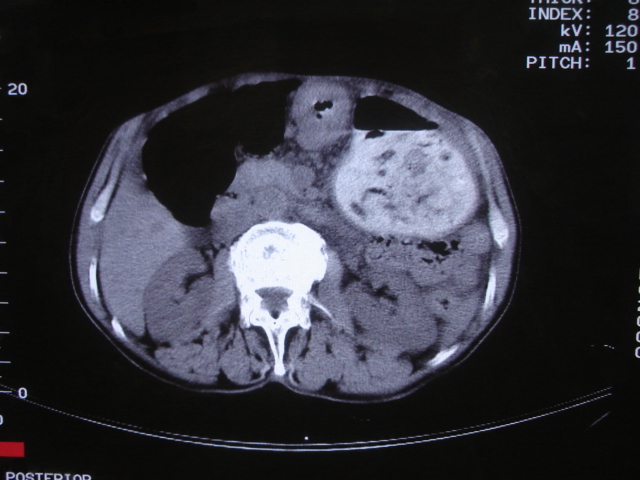

以下是引用深泽交通医院在2008-7-17 12:39:00的发言:[br]胃下垂;胃窦占位